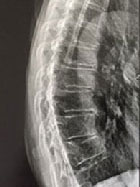

Quand la cascade fracturaire est trop rapide pour consulter le rhumatologue

Dr Jacques Fechtenbaum Hôpital Cochin - Paris

Mme B.A., née le 05/05/1947, psychologue, sous THS jusqu’en 2012, stoppé lors d’un AVC résolutif, consulte un rhumatologue pour la première fois en février 2016. Elle a bénéficié d’une ostéodensitométrie en 2007 : T-score rachis = -1,5DS ; T-score total col = -1,4DS ; T-score col = -1,2DS...